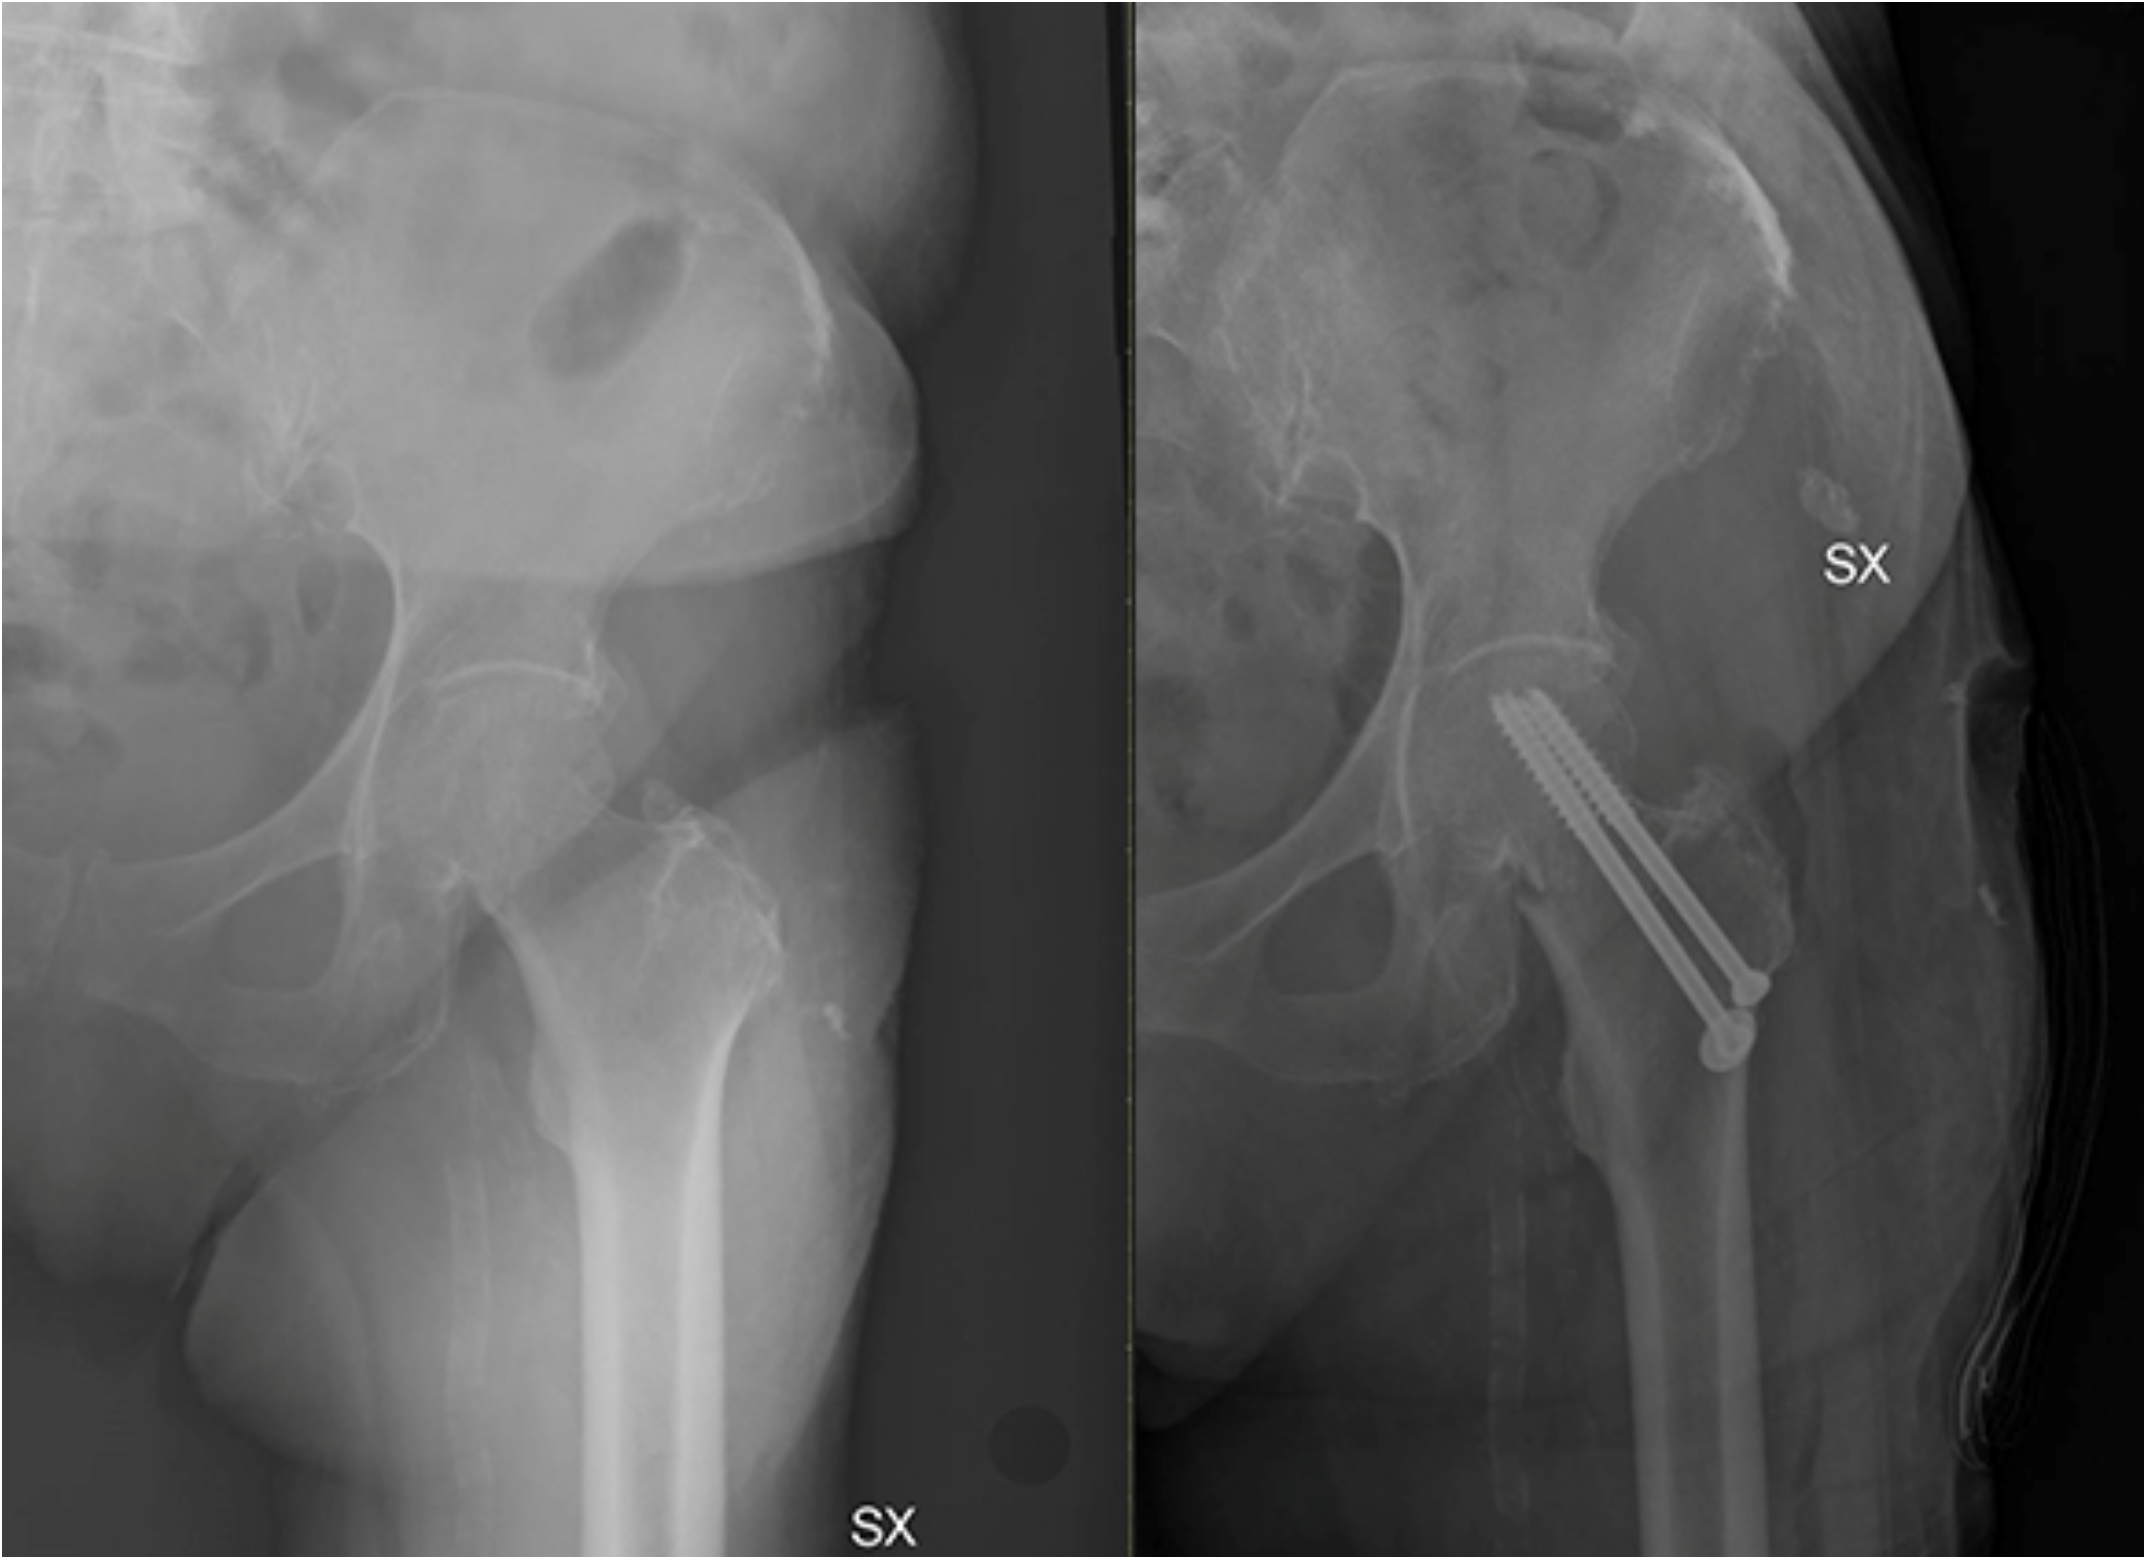

5. Surgical Management